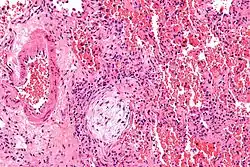

Micrograph showing a Masson body (off center left/bottom of the image – pale circular and paucicellular), as may be seen in cryptogenic organizing pneumonia. The Masson body plugs the airway. The artery associated with the obliterated airway is also seen (far left of the image). H&E stain.

Organizing pneumonia is usually preceded by some type of lung injury that causes a localized denudation or disruption in continuity of the epithelial basal laminae of the type 1 alveolar pneumocytes that line the alveoli.[9] This injury to the epithelial basal lamina results in inflammatory cells and plasma proteins leaking into the alveolar space and forming fibrin, resulting in an initial fibroblast driven intra-alveolar fibroproliferation.[9] The fibroblasts differentiate into myofibroblasts and continue to form fibrosis resulting in intra-alveolar fibroinflammatory buds (Masson's Bodies) that are characteristic of organizing pneumonia.[9] These Masson's bodies consist of inflammatory cells contained in an extracellular matrix consisting of type I collagen, fibronectin, procollagen type III, tenascin C and proteoglycans.[9] Angiogenesis , or the formation of blood vessels, occurs in the Masson's bodies and this is driven by vascular endothelial growth factor.[9] Remodeling occurs, resulting in the intra-alveolar fibroinflammatory buds (Masson's Bodies) moving into the interstitial space and forming collagen globules that are then covered by type 1 alveolar epithelial cells with well developed basement membranes. These type 1 alveolar epithelial cells (pneumocytes) then proliferate, restoring the continuity and function of the alveolar unit.[9] This process is in contrast to the histopathologic changes seen in usual interstitial pneumonia where extensive fibrosis and inflammation occur leading to fibroblastic foci to form in the alveolar spaces resulting in obliteration of the alveolar space, scarring and significant damage to lung architecture (the alveoli).[9]

Biopsy findings in patients with organizing pneumonia consist of loose connective tissue plugs involving the alveoli, alveolar ducts and bronchioles. The loose connective tissue plugs occupying the alveolar spaces often connect to other connective tissue plugs in nearby alveoli via the pores of Kohn creating a characteristic butterfly pattern on histology.[9] There is usually minimal to no interstitial inflammatory changes in biopsies of organizing pneumonia.[9]

Histologically, cryptogenic organizing pneumonia is characterized by the presence of polypoid plugs of loose organizing connective tissue (Masson bodies) within alveolar ducts, alveoli, and bronchioles.